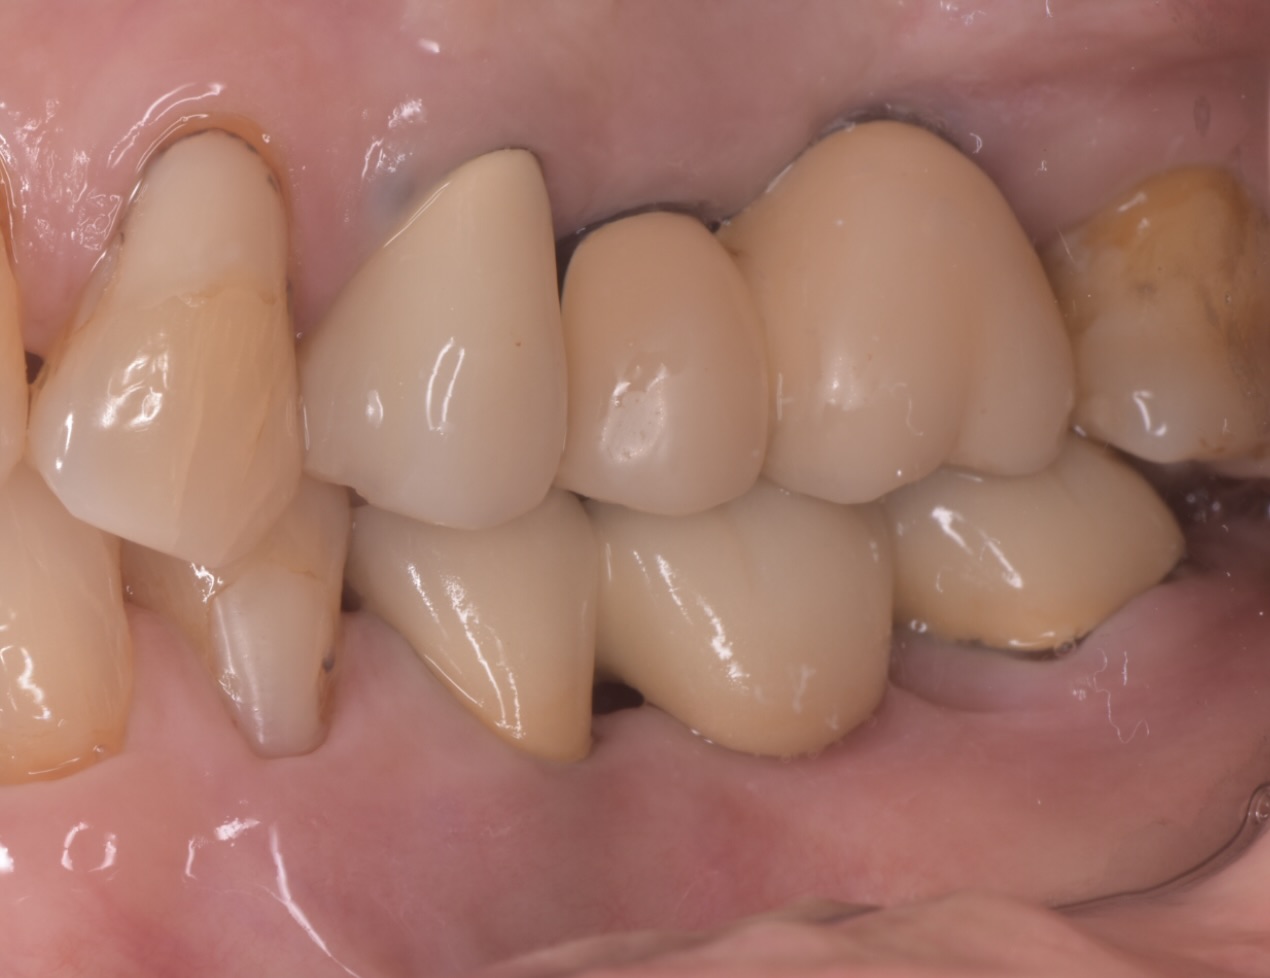

問題なかったので最終的なセラミックの上部構造をセットしました。

現在問題なく2年程経過し

入れ歯にせず快適に咬めて満足しているとのことです。

2年程経過し、2本とも周囲炎にもならず問題無く機能しています